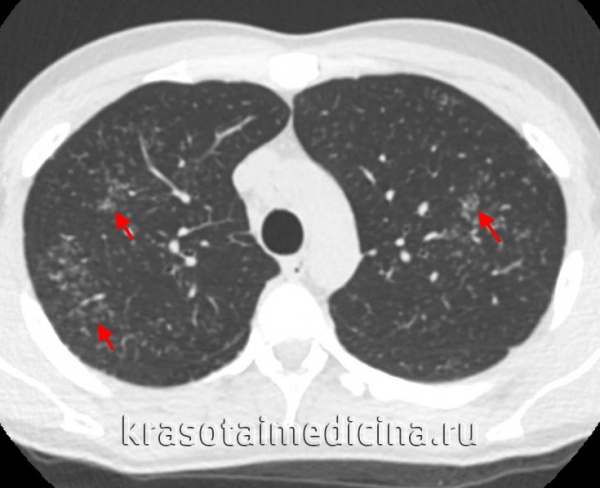

• Компьютерная томография (КТ) органов грудной клетки:

- При КТ органов грудной клетки можно выявить лимфадепопатию или гранулематозную инфильтрацию.

- Другие признаки могут включать наличие малых узелков с бронховаскулярной или субплевральной локализацией, утолщение междолевой плевры, легочную ткань в виде «медовых сот», бронхоэктазы и альвеолярную консолидацию.

КТ органов грудной клетки. Множественные типичные саркоидозные очаги субмиллиметрового диапазона с диффузным распространением